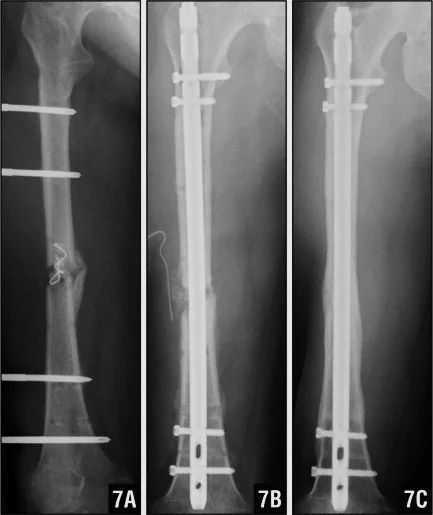

Femoral Shaft Fractures

Mechanism and Complications

- Mechanism: high energy

- Bleeding:

- Can easily loose 2L of blood

- Need good resuscitation

- Early fixation

- Inability to bear weight

- Risk of thrombo-embolism

- X-rays:

- AP & lateral radiographs

- Two joints (above and below)

- Very important

Surgical Treatment

- IMN: Intramedullary nail / Locked(with screws)

- The treatment of choice

- Relative stability

- Allows early weight-bearing